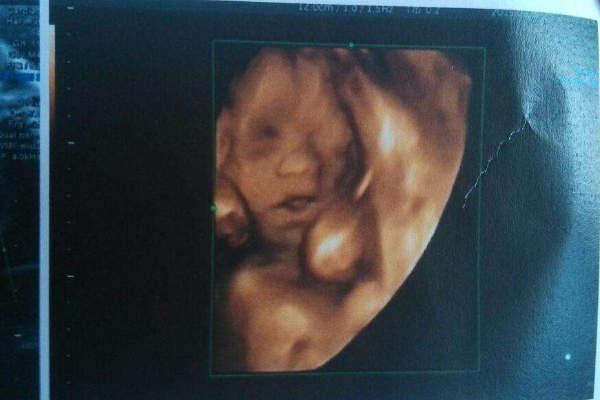

英国科学家发现,婴儿并不是在出生后才学会笑的,而是在出生前数周就学会了微笑。科学家在使用4D彩超时,已经捕捉到难得一见、胎儿出生前微笑的画面,而且还看到他们会眨眼。

胎儿为何会笑?专家认为这是一种情绪或生理反应,为帮助胎儿出生后适应外面的世界所做的准备。但出生后数周的婴儿为什么却不会笑?对此研究专家解释为,这种现象可能意味着胎儿在子宮中时是无忧无虑的,不受到什么干扰,而出生后数周内因置身于一个全新的陌生环境中,使他们受到了一些“创伤”,所以他们就不会笑了。